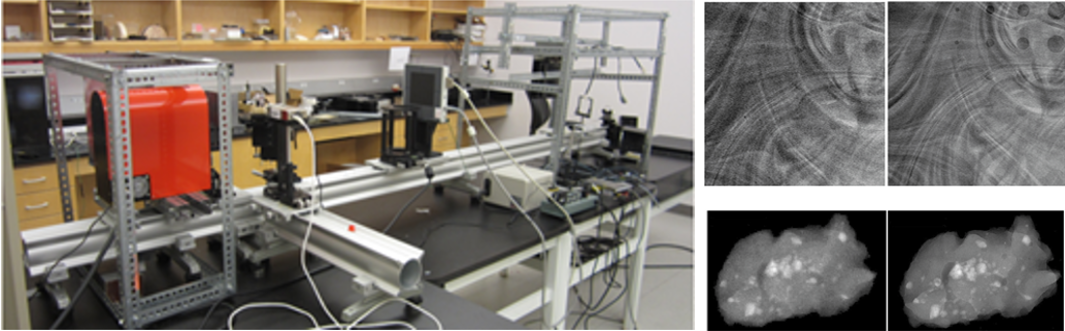

This Core aims to implement an interdisciplinary management plan to build an optimal infrastructure for supporting medical imaging related translational cancer research projects, including providing service using the existing imaging equipment and developing new investigative imaging testbeds and quantitative image feature analysis tools. Thus, this Core is not merely a collection of the existing imaging equipment in a distinct space; it also allows us to fully network our current research expertise to provide experienced support as we move from basic studies into more innovative translational research projects that could benefit cancer patients in the future.